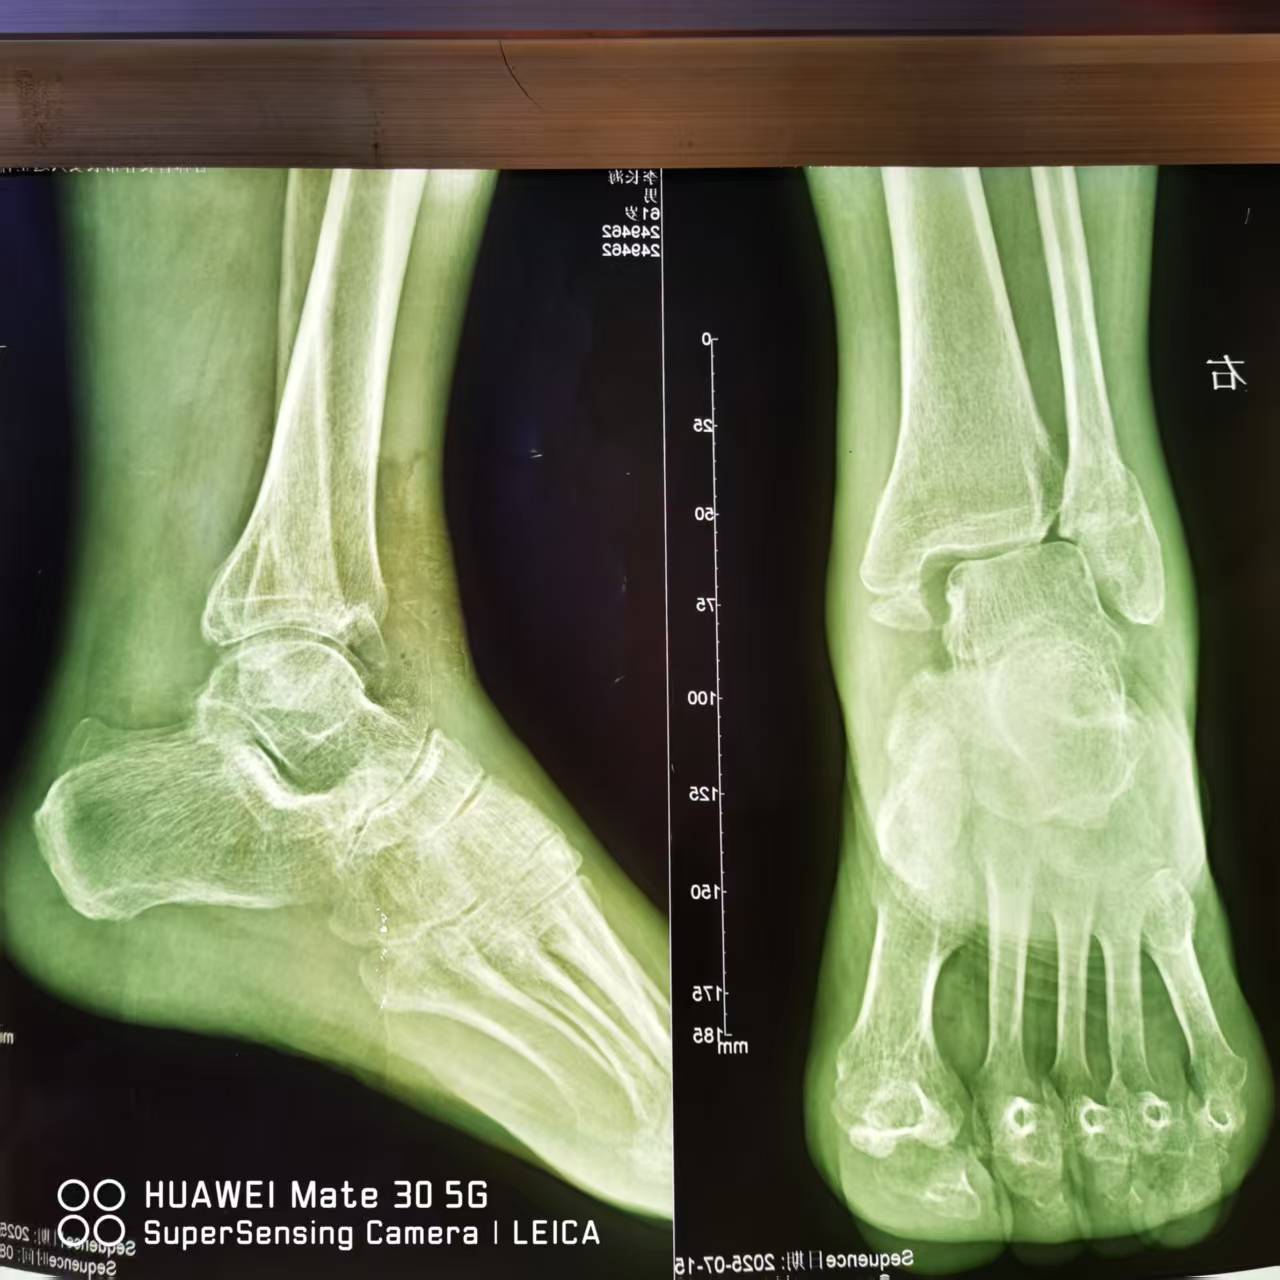

GUIDE 7月21日 我院骨科团队成功为一位患者实施了高难度的右踝关节陈旧性骨折及半脱位手术。该手术的顺利完成,不仅彰显了我院骨科在复杂足踝疾病治疗领域的技术实力,更为广大患者带来了康复的希望。 家住大岭镇的李XX,今年1月份在自家院子里行走,因地面有积雪不愖滑倒,当时右脚脖感觉异常疼痛且肿胀畸形,不能站立行走,李XX受伤后被送到卫生院就诊,摄片显示右踝关节骨折,李XX没想住院治疗,便去了一家私人诊所进行了复外固定,固定后也没有按时复查,后来在平时行走中,感觉右脚脖疼痛明显。 6月份李XX去了医院复查DR片,显示右踝骨折畸形愈合,踝关节半脱位,医生建议他进行手术治疗。于是李XX来到阳光医院,经检查后,以“右踝关节陈旧性骨折,右踝关节陈旧性半脱位”收入骨科住院治疗。 患者右踝摄片 2025/7/15 入院后,我院骨科团队对患者病情进行了全面而细致的评估。通过影像学检查,清晰地了解了骨折部位、脱位程度以及周围软组织损伤情况。考虑到患者骨折时间较长,部分骨折已畸形愈合,加之踝关节半脱位明显,手术难度较大。但患者对恢复踝关节功能的期望很高,经过骨科团队反复讨论,并与患者及家属充分沟通后,最终制定了个性化的手术方案。 03 7月21日下午,我院骨科团队为李XX于腰硬联合麻醉下行右外踝切开截骨复位锁定钛板螺钉内固定,内踝切开截骨复位拉力螺钉内固定,术后摄片效果满意。 04 患者术后右踝摄片 术后,患者被转入骨科病房进行密切观察和护理。此次手术的成功,再次证明了我院骨科在复杂足踝疾病治疗方面的卓越能力。专家提醒,踝关节外伤后应及时就医,进行规范的诊断和治疗,避免延误病情导致陈旧性损伤,增加治疗难度和患者痛苦。 专 家 简 介 董庆武 主任医师 毕业于吉林大学医疗专业,后在公主岭市中心医院骨科从事临床工作。曾在北京304医院进修学习创伤骨科。擅长骨科疾病的诊断治疗。熟练掌握四肢骨折的切开、闭合复位手术内固定。熟悉手外伤的诊疗及皮肤缺损的创面覆盖。发表国家级论文多篇。 谭志远 副主任医师 毕业于延边大学医学院,拥有超过20多年的骨科临床经验。曾于吉林大学第一医院骨科学进修,积累了丰富的专业知识与实践经验。擅长四肢骨折的手法复位、夹板石膏外固定及切开复位内固定治疗,能够独立完成复杂的四肢关节手术及人工